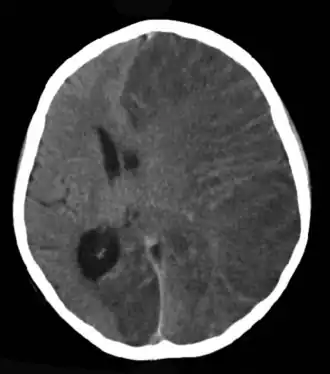

![]() КТ головного мозга 8-летней девочки с энцефалитом Расмуссена в острой стадии. | |